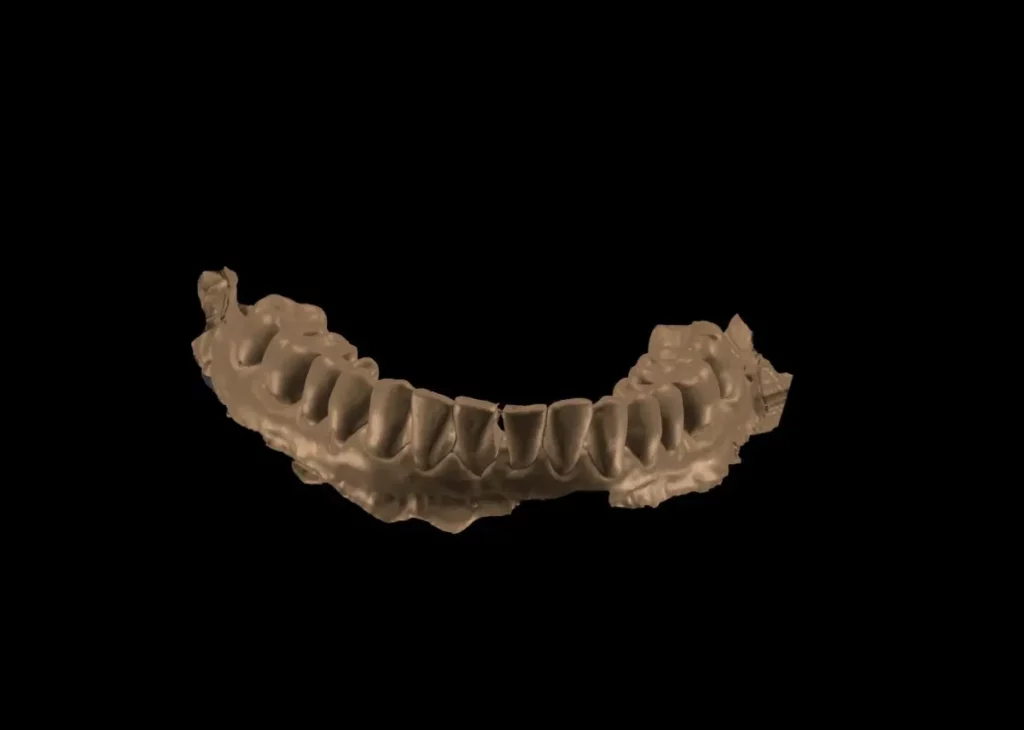

Mediante un TAC dental en 3D y un escáner intraoral, analizamos la anatomía del paciente y planificamos la posición exacta de los implantes en función de la planificación protésica.

Mediante software especializado planificamos la posición ideal de los implantes teniendo en cuenta la futura prótesis dental.

Esto permite diseñar el tratamiento con máxima precisión antes de la cirugía.